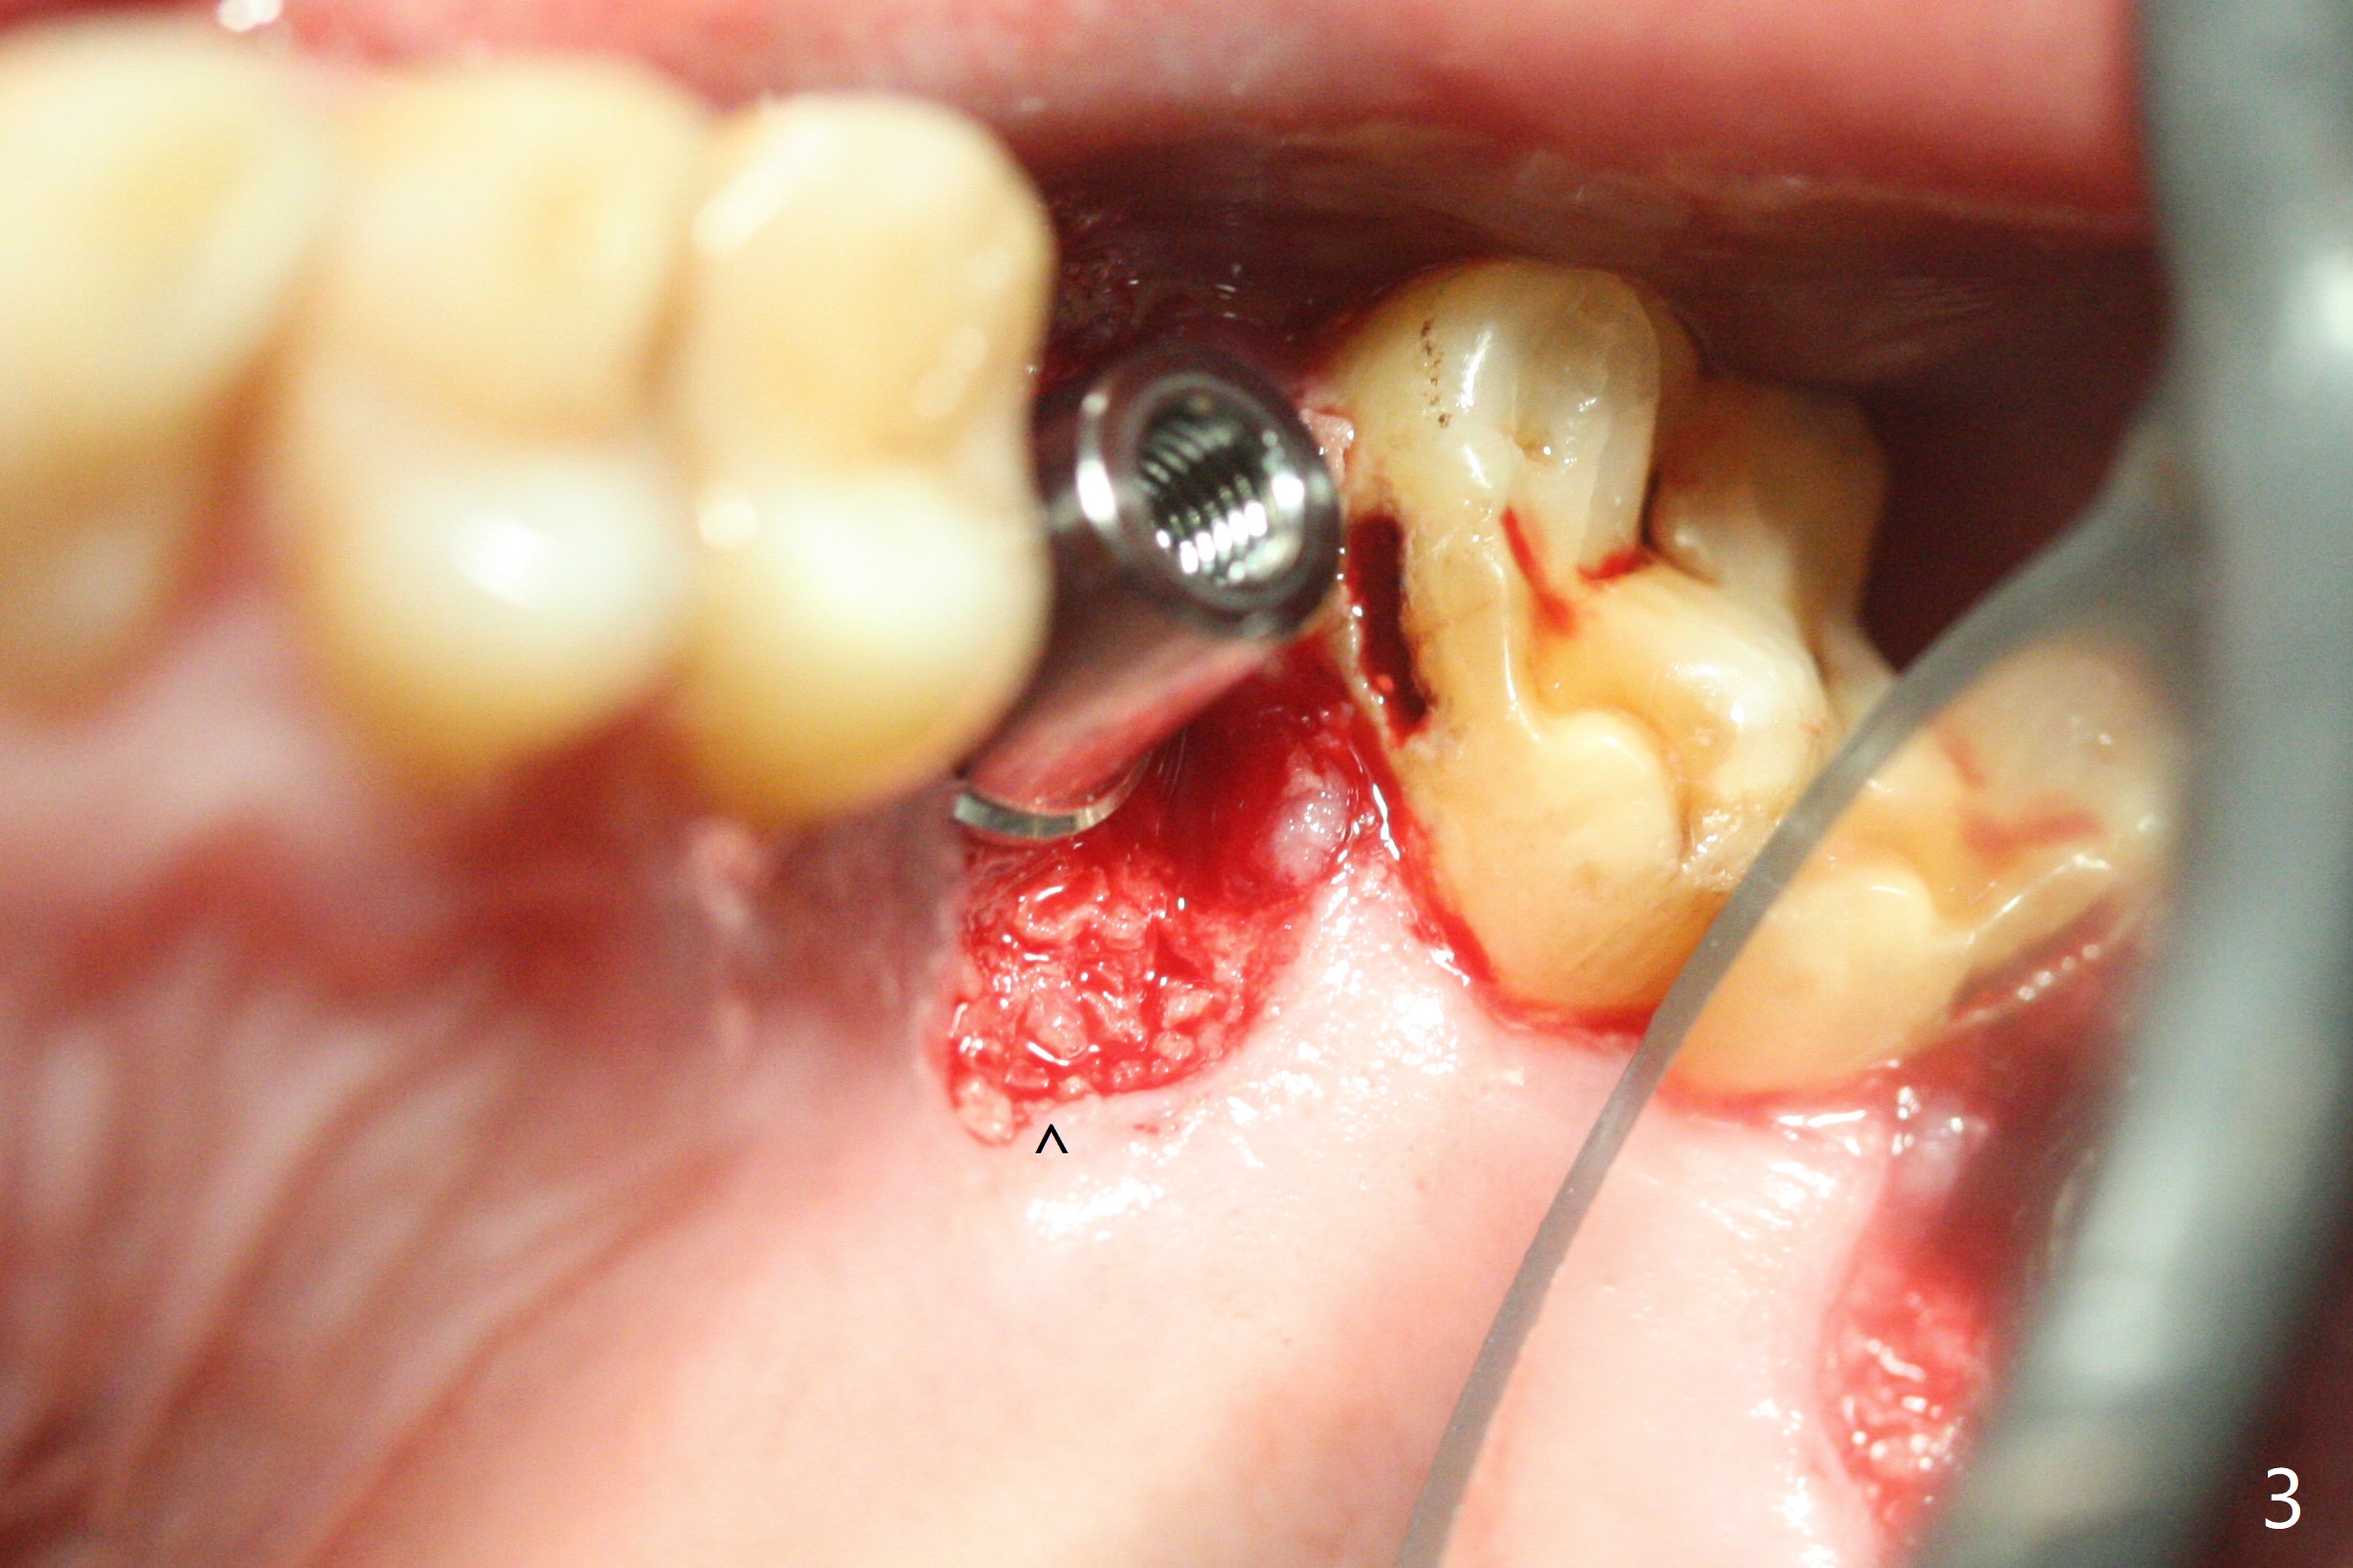

With modification of drill sequence in the last 3 steps (4.5x7.3, 4.0x8.5 and 3.5x10 mm drills) at #14 and sinus lift (Fig.1), a 5x9 mm implant is placed with ~ 50 Ncm following back up twice. Sticky bone mixed with autogenous bone (Fig.1,2 white *) is placed in the sockets before and after placement of a 6.5x5.7(2) mm abutment. Since the palatal gingival margin is recessive (Fig.3 ^), a palatal socket shield retains to prevent further recession (Fig.4 in the end of periodontal probe). Because the margin of the abutment is low, it changes to one with longer cuff (Fig.5). An immediate provisional is fabricated (Fig.6,7 P). The bone graft is indistinguishable from the original alveolus 9 months postop (Fig.8 *). The palatal socket shield is exposed 10 months postop (Fig.9 <). Since the implant is intentionally placed buccal; the sheath is not essential.